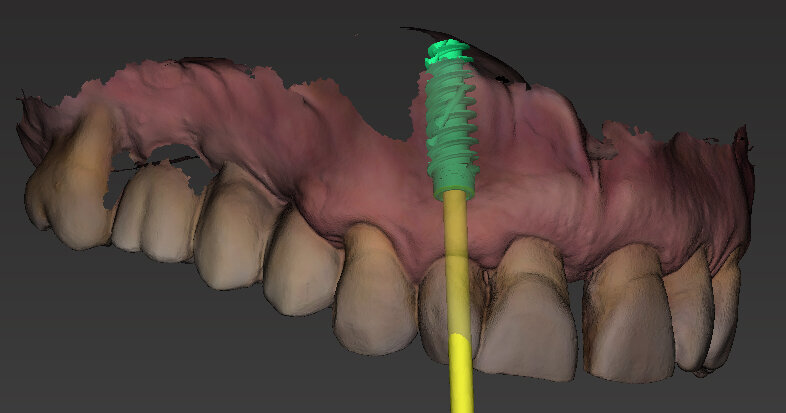

Il piano di trattamento prevede l’estrazione degli elementi dentali, l’inserimento di due impianti e la realizzazione di una protesi fissa di quattro elementi. Il problema da gestire è quello della fase provvisoria. Non è ipotizzabile una protesi mobile e quindi programmiamo di inserire subito dopo l’intervento un provvisorio immediato. Questo ci consente di condizionare da subito i tessuti periimplantari e anche le zone dei ponti. Si rileva un’impronta digitale (Figg. 5, 6), e la programmazione degli impianti viene effettuata con un software di chirurgia guidata (Fig. 7) e la posizione degli impianti nello spazio biologico e nello spazio protesico viene fatta sulla base di una ceratura diagnostica (Figg. 8, 9). Inseriamo gli impianti virtuali nell’osso disponibile (Figg. 10-13) e in relazione all’aspetto protesico correggiamo l’asse di inclinazione degli impianti con componenti secondarie angolate a 17° (Figg. 14, 15). Questo ci consentirà di realizzare una protesi avvitata con i fori situati nella zona palatale.

Fig. 10 - Posizionamento virtuale dell’impianto 1.2.

Fig. 11 - Posizionamento virtuale dell’impianto 2.2.

Il nostro obiettivo è quello di riuscire a dare alla paziente un provvisorio immediato nell’arco di due ore. Questo diventa possibile perché abbiamo utilizzato un flusso digitale fin dall’inizio. In laboratorio vengono realizzate la dima chirurgica (Figg. 16, 17), la dima protesica (Fig. 18) e anche il provvisorio (Figg. 19-21) che contiene delle alette di riposizionamento. Il tutto gestito con modelli digitali sui quali saremo in grado di funzionalizzare il provvisorio post-chirurgico (tecnica DIL). In un caso come questo se utilizziamo un flusso digitale possiamo evitare subito dopo la chirurgia di rilevare un’impronta degli impianti inseriti. Infatti, utilizziamo una dima chirurgica che ci faciliterà le fasi di intervento. La dima ci consentirà di non fare lembi e nessuna incisione di rilascio (Fig. 22), dopo aver inserito gli impianti (BLX Straumann) (Figg. 23-31) e aver controllato il loro alloggiamento, inseriamo sugli stessi dei transfert da impronta (Fig. 32).

Fig. 23- Posizionamento della dima.